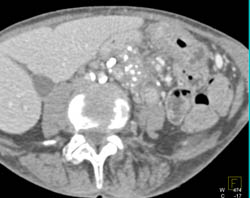

Splenic Tissue Simulates An Islet Cell Tumor